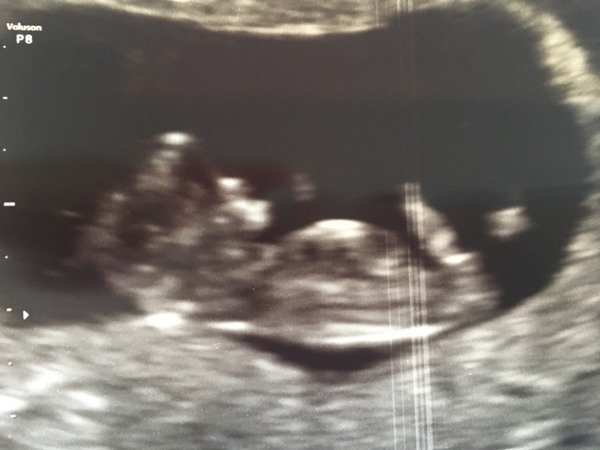

We are planning on telling friends and family this week over half term, our nhs scan is quite late at over 13 weeks so went for a private one yesterday and got moved forward a couple of days... Cant believe how clear this is for 11 weeks!

Nev, that's such a good clear picture! I do love it that people are getting dated a bit ahead of what they thought. Really hope that happens to us too!

Thanks pink i was amazed with that picture! I have a dvd recording too its incredible to see them wiggling around and waving!

Aww Nev it's a lovely clear photo. My first private scan was at 8 weeks so it's a pizza slice! I was pushed back a day with my 12 weeks but hoping to not change or come forward with my 20 weeks.

Amazing picture nev!

Oh, and lovely scan Nev! All looking good in there Smile